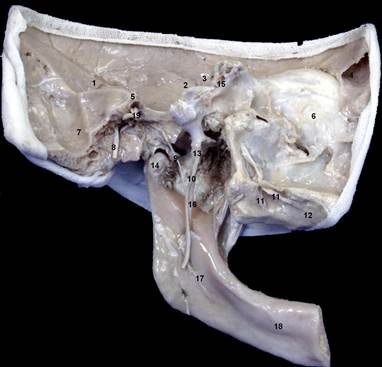

Рис. 7_номерки